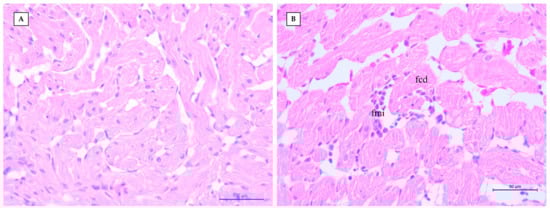

| 1 | FCD (<10% TS) | MiMI (<10% TS) | MiMI (<10% TS) | MiMI (<10% TS) | FCD (<10% TS) | MiMI (<10% TS) | FCD (<10% TS) | <10% TS | <10% TS |

| 2 | FCD (10–50% TS) | MoMI (10–50% TS) | MoMI (10–50% TS) | MoMI (10–50% TS) | FCD (10–50% TS) | MoMI (10–50% TS) | FCD (10–50% TS) | 10–50% TS | 10–50% TS |

| 3 | DCD (>50% TS) | SMI (>10% TS) | SMI (>10% TS) | SMI (>10% TS) | DCD (>50% TS) | SMI (>10% TS) | DCD (>50% TS) | >50% TS | >50% TS |